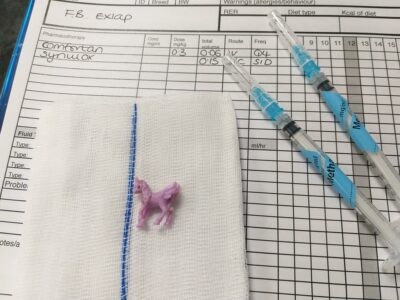

fine needle aspiration - cytology

fine needle aspiration - cytology -